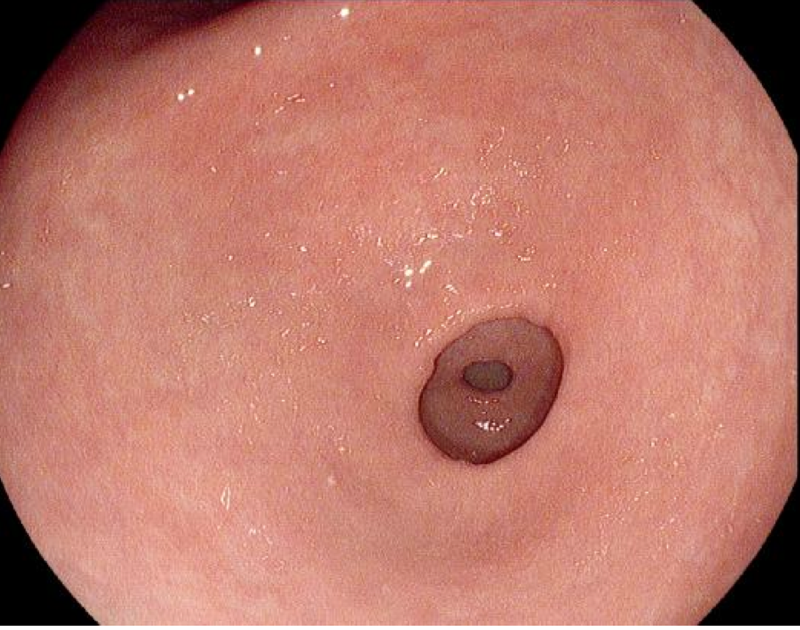

内镜分辨率越高,就能够展现更多的细节,细节对胃肠病的诊断有什么用呢?用处太大了。关注过前面关于早期胃癌诊断方面文章的朋友,应该已经知道:做胃镜的一个重要意义是发现还没有症状的早期胃癌。而早期胃癌相对进展期的胃癌,面积更小,表面和周围正常粘膜基本平行,既不明显隆起也不明显凹陷。但是如果仔细看,就会发现这个地方和周围不太一样。怎么不一样?是胃小凹不一样。从胃镜下看,胃粘膜是非常光滑的,但放大了看,或者分辨率足够高的时候,就会发现其实一点也不光滑,有很多规则排列的凹陷的小孔,或者突起的像鹅卵石一样的结构,这就是正常的胃小凹。而早期胃癌的胃小凹因为癌细胞的侵犯,胃小凹变得很不规则,甚至完全消失。如果用老式的胃镜,分辨率比较低,就可能发现不了这样细微的变化。而新式的高分辨率的胃镜,再配上一个大的显示屏,胃小凹分毫毕现。这样的变化自然更容易发现。第一次用高分辨率内镜的感觉,就像我第一次看高清压制的《王者归来》,居然发现每个兽兵脖子上都系着一条恶心的领巾,之前看过多次普通DVD压制的都没有注意。

放大内镜则是在高分辨率内镜基础上发展起来的。不过有的高分辨率内镜装备了,大部分却没有装备。高分辨率内镜是自动对焦的,随着目标和镜头的远近自动调焦,保持影像清晰。想看到更清晰的细节就得靠的近些,但靠的过近,自动调焦就无法实现了,就需要固定一个焦距。放大内镜在靠的很近时会启动另外一个固定焦距,这个焦距是不能自动调节的,所以往往需要加一个透明帽,顶到胃粘膜上时,使粘膜和镜头保持一个固定的距离。

高分辨率内镜

放大内镜